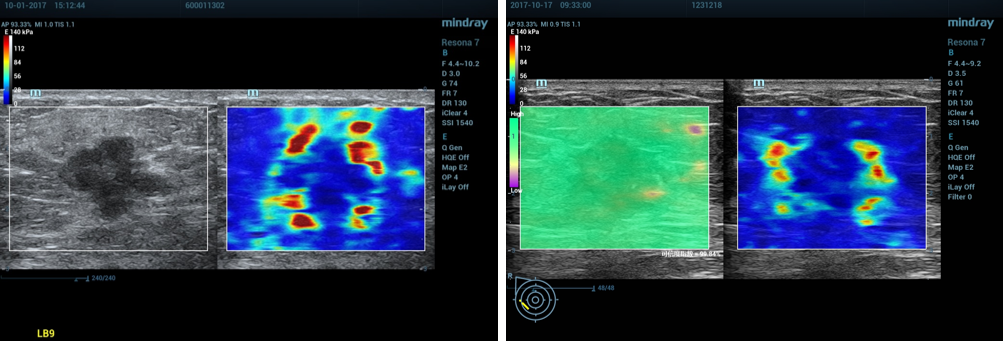

4、正确操作示范:

①乳腺剪切波弹性成像